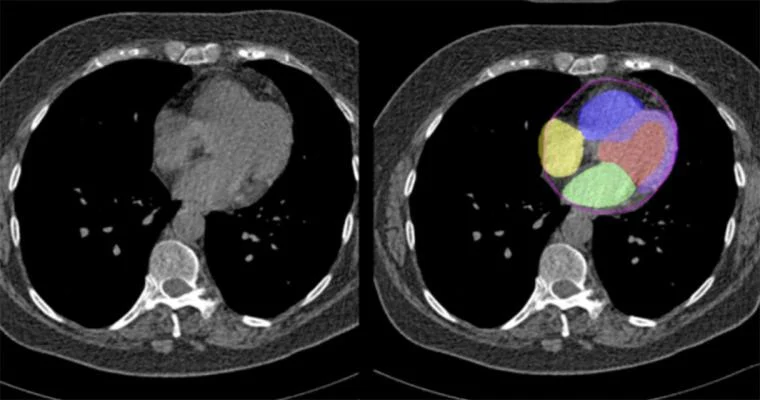

For example, recent research shows that advanced AI models can estimate cardiovascular risk directly from routine CT scans, without the need for extra tests. This approach could make identifying cardiovascular risk less expensive and less invasive, while helping clinicians spot early warning signs sooner. The accuracy of these predictions depends heavily on how well medical data is labeled during training.

Trained AI Models Evaluating Cardiovascular Risk Using CT Scan Data (Source)